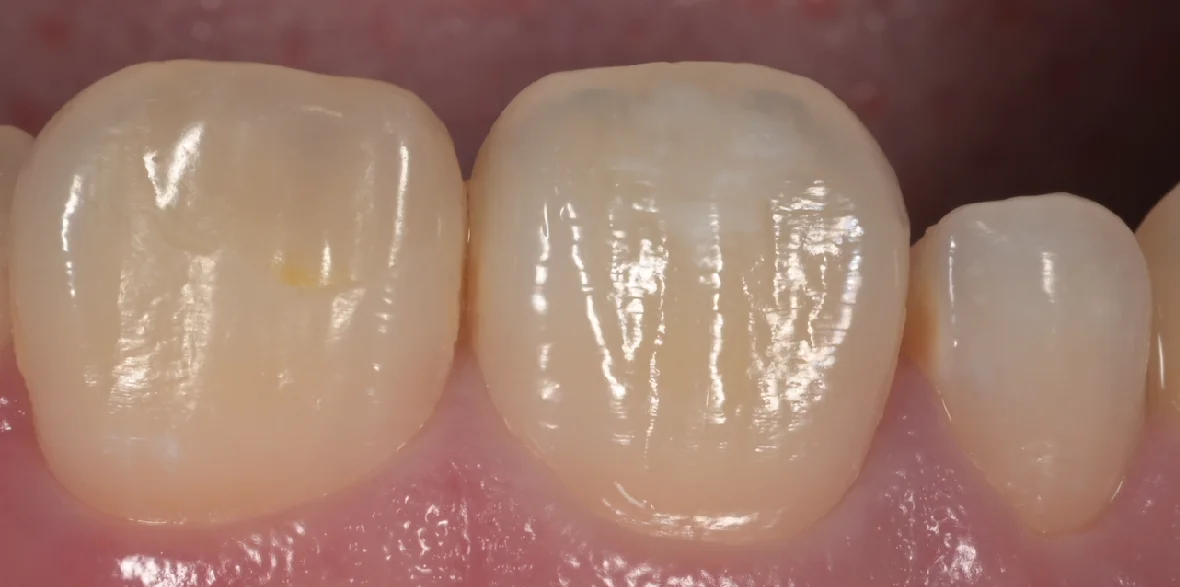

術後写真がこちらになります。

ICON治療にてホワイトスポットを改善。|坂寄歯科医院(取手市藤代) - 画像4

塩酸で歯の表層のエナメル質を一層溶かしながらそれをブラシで擦りつつ、エナメル質内部に存在している空気の層への通り道を作って・・・その通り道を通して、内部にレジンを流し込むのがこのICONという治療です。

さて、ラバーダムを外したのがこちらになります。

ICON治療にてホワイトスポットを改善。|坂寄歯科医院(取手市藤代) - 画像5

随分と目立たなく、違和感が少なくなったのが分かるかと思います。

術前術後です。

ICON治療にてホワイトスポットを改善。|坂寄歯科医院(取手市藤代) - 画像6